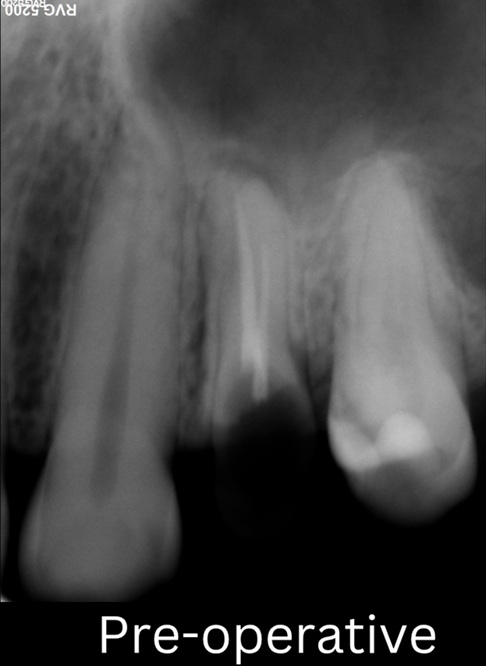

Pre-operative Radiographs: Pre-operative periapical radiographs were taken to evaluate the existing treatment, identify the cause of failure (poorly condensed gutta-percha/inadequate obturation), and assess the periapical status.

pre operative situation

pre operative xray demonstrating the poor g.p and a p.a lesion